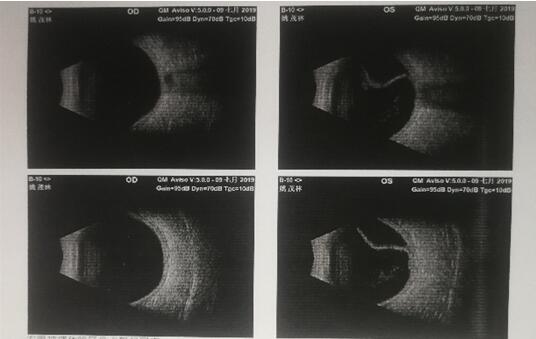

姚老师术前检查视网膜脱落

术后恢复正常

经过严格的分析、对比和确认,姚老师被确诊为“左眼孔源性视网膜脱离”,胡院长告诉姚老师可以得到有效治疗但是不能拖,要“早发现,早治疗”,胡院长建议第二天马上做手术,“姚老师这个病情很严重,幸好来的及时,才避免了造成更加严重的后果。”胡院长介绍。